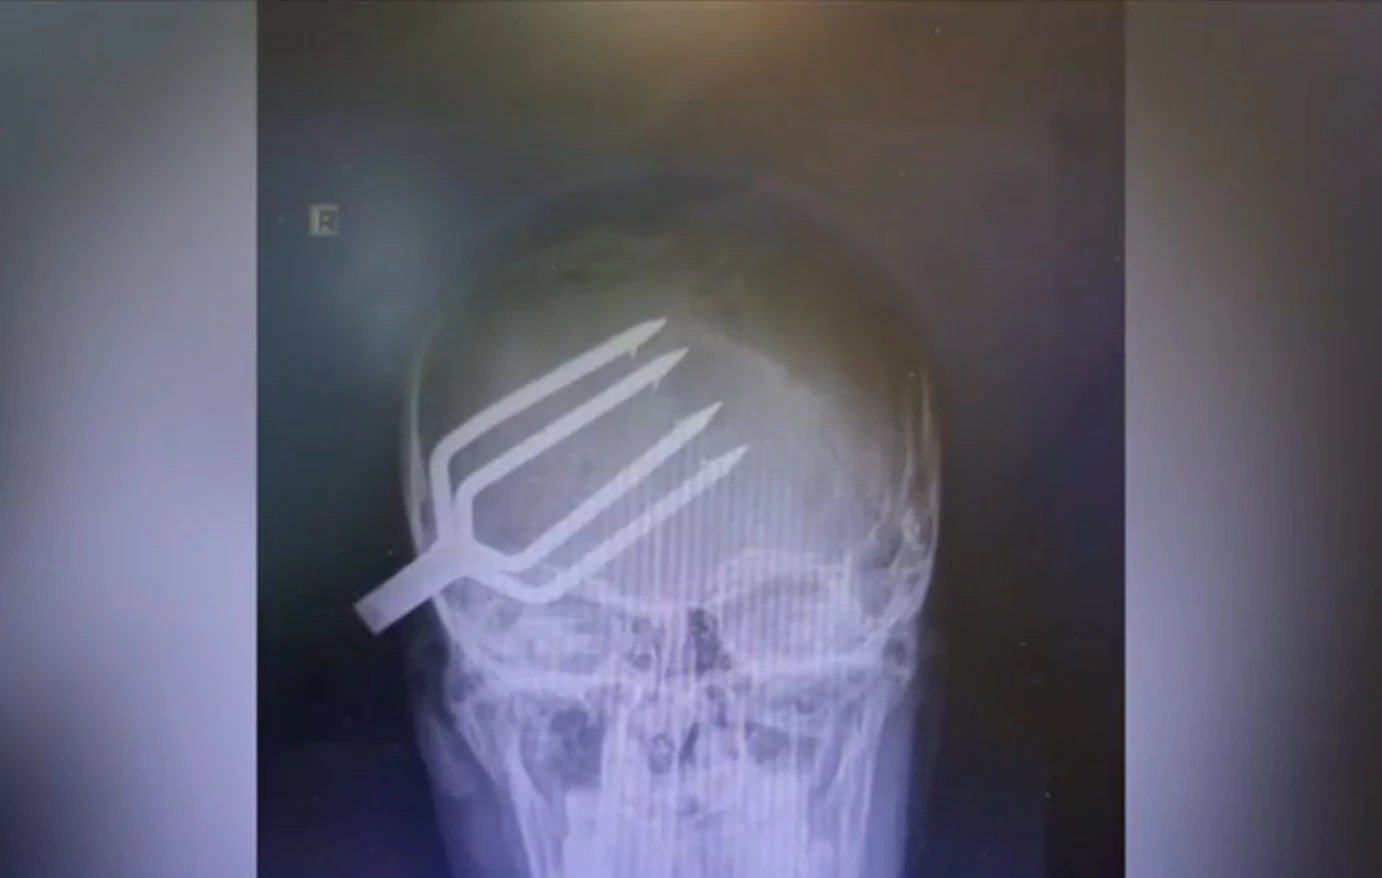

Βγήκε από το νοσοκομείο ο 14χρονος που του είχε καρφωθεί καμάκι από ψαροντούφεκο στο κρανίο

Ήταν τυχερός γιατί για χιλιοστά το τραύμα δεν απέβη μοιραίο

Εξιτήριο πήρε ο 14χρονος που είχε τραυματιστεί σοβαρά στο κεφάλι από καμάκι ψαροντούφεκου στη Χαλκιδική.

Ομάδα παιδιών έπαιζαν όταν καρφώθηκε το καμάκι στο κρανίο του 14χρονου. Σύμφωνα με τον Alpha, ο 14χρονος ήταν τυχερός γιατί για χιλιοστά το τραύμα δεν απέβη μοιραίο.

Ειδική ομάδα γιατρών αφαίρεσε το καμάκι από το κρανίο του και το παιδί πήρε εξιτήριο  σήμερα από το νοσοκομείο.